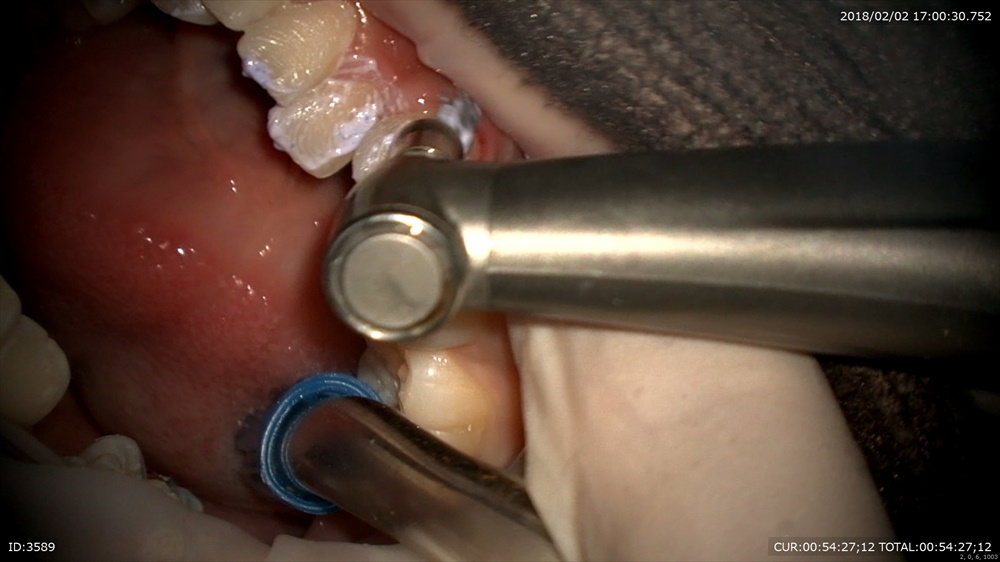

矯正から。今日が装置装着の初日。当院は通常分ける作業を1日で、すべてやります。抜歯→TPA装着→DBS→ワイヤー装着

クリーニング

TPA装着、DBS